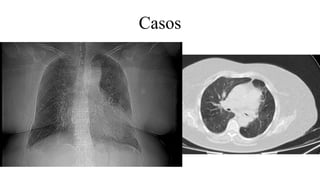

Casos

Jornadas cemic 2020